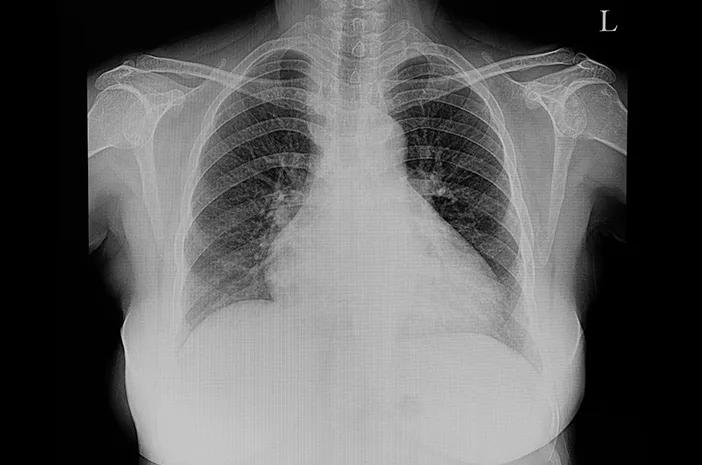

Ada dua jenis utama pembengkakan jantung, yaitu hipertrofi dan dilatasi. Hipertrofi terjadi ketika otot jantung menebal, sedangkan dilatasi terjadi ketika ruang jantung melebar. Kedua kondisi ini merupakan respons alami dari jantung terhadap beban kerja yang berlebihan. Meski tidak selalu menimbulkan gejala, kondisi ini tetap perlu diperiksa melalui pemeriksaan medis seperti rontgen dada atau USG jantung.